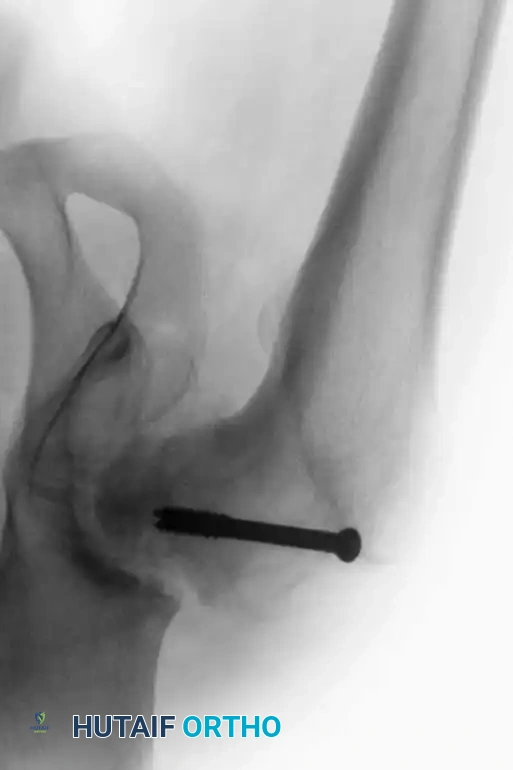

Arthrodesis with Hip Compression Screw Fixation

Pagnano and Cabanela popularized the use of a sliding hip compression screw (dynamic hip screw) supplemented by cancellous screws. This construct offers several distinct advantages:

1. It ensures the hip is fused in the proper position, minimizing low back pain.

2. It provides dynamic compression across the fusion site, promoting primary bone healing.

3. It avoids bulky hardware that might damage the abductor muscles, preserving them for future THA.

4. It minimizes the need for postoperative spica casting.

Intraoperative fluoroscopy demonstrating the trajectory of the sliding hip compression screw across the denuded joint space.

Technique Overview:

Following standard joint denudation, the hip is positioned optimally. A guide wire is passed from the lateral proximal femur, through the femoral neck, and deep into the thickest portion of the ilium (above the acetabular dome). The tract is reamed, and a large lag screw is inserted. A side plate is applied to the lateral femur, and compression is achieved. Two or three additional cancellous screws are placed proximal to the hip screw to provide rotational stability.

Final construct showing the dynamic hip screw and supplementary anti-rotation cancellous screws.